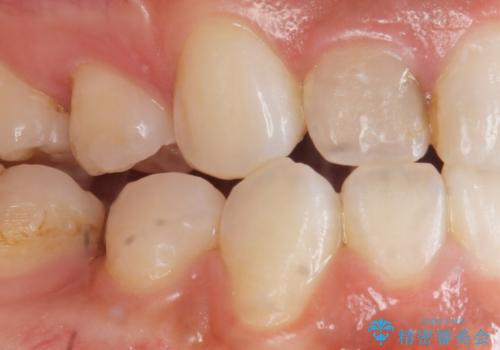

精査したところ、右上の側切歯(右上2)は神経が死んで変色しており、左上の側切歯と犬歯の間に2mm程度の隙間を認めました。

矯正せずに早く治したいという強いご希望により、セラミッククラウンによる補綴治療(上顎両側2の2本)を行いました。

- ¥396,000 (根管治療・土台×1本、仮歯・クラウン×2本) ※税込費用は治療当時の料金となります